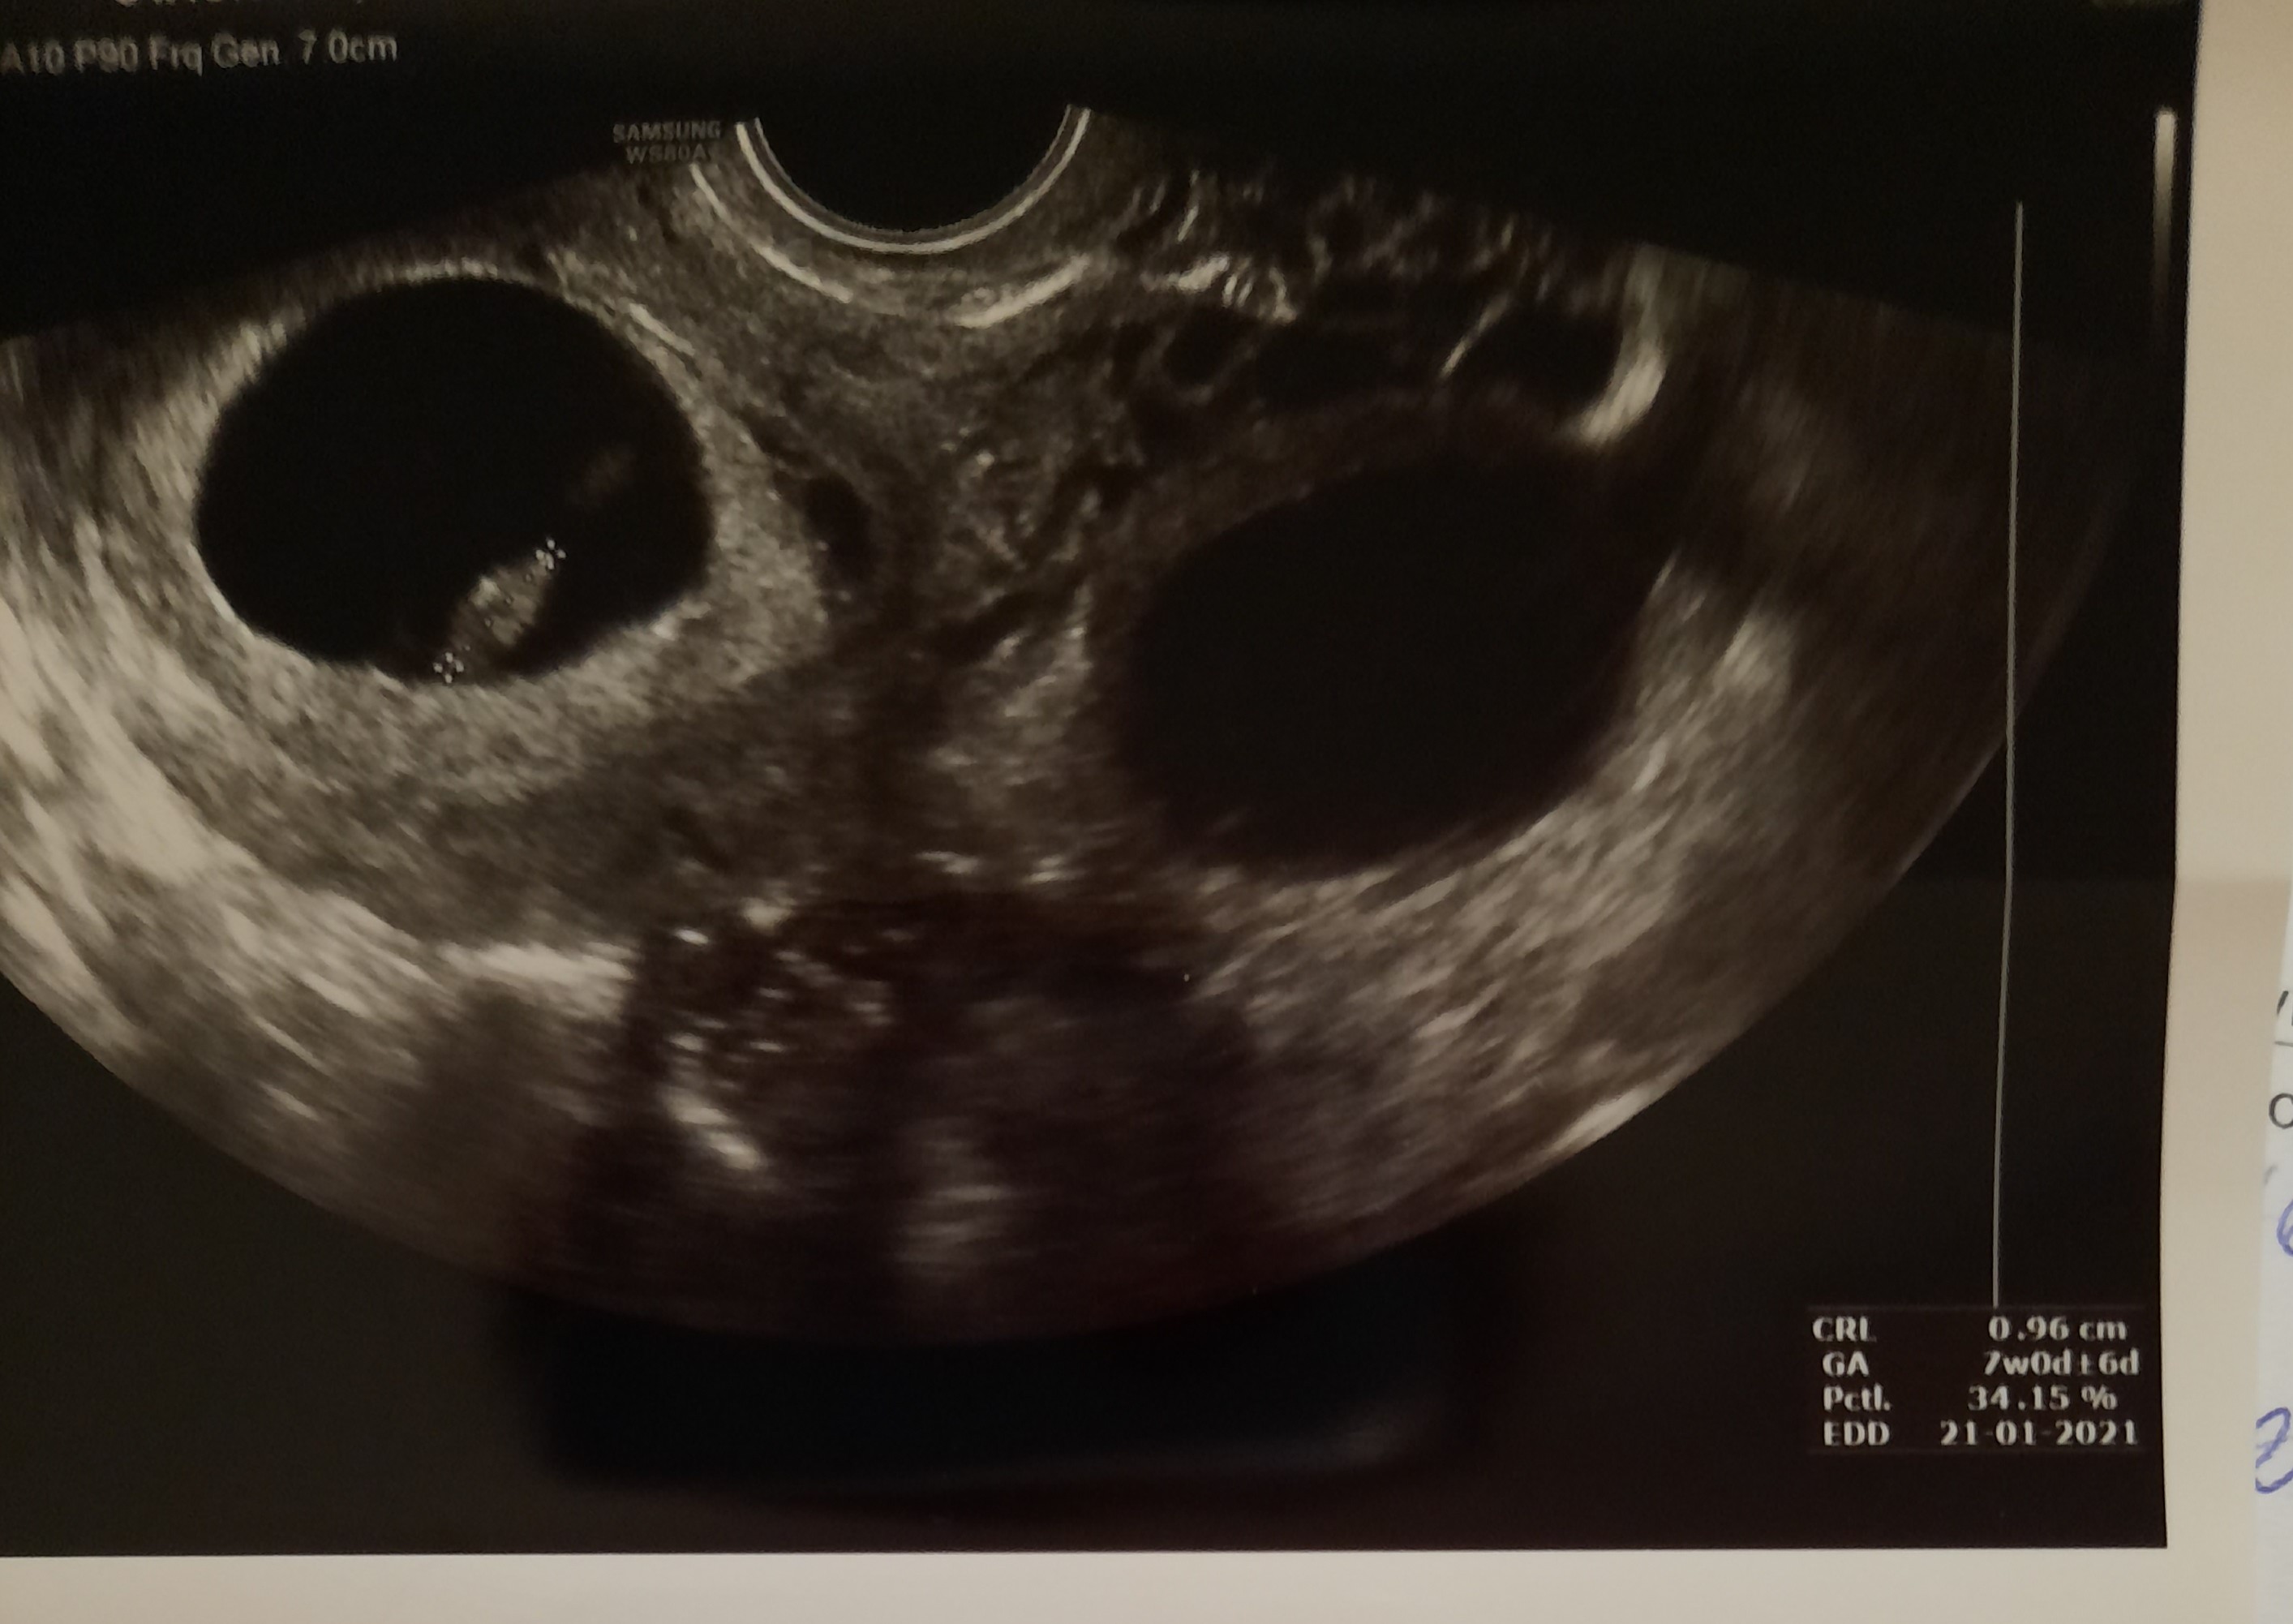

Zrobiłam dziś kolejny test po kilku dniach kreska moim zdaniem o wiele ciemniejsza od tamtych. Dziś odbieram wyniki z pierwszej bety i robię druga a w czwartek chwila prawdy wizyta z wynikami u doktora ale ten niby torbiel lekko dokucza mi ból pleców i pieczenie rwanie w podbrzuszu okresu nadal brak ani krwawienie i oby już nie przyszło 😹

Zrobiłam dziś kolejny test po kilku dniach kreska moim zdaniem o wiele ciemniejsza od tamtych. Dziś odbieram wyniki z pierwszej bety i robię druga a w czwartek chwila prawdy wizyta z wynikami u doktora ale ten niby torbiel lekko dokucza mi ból pleców i pieczenie rwanie w podbrzuszu okresu nadal brak ani krwawienie i oby już nie przyszło 😹Zobacz załącznik 1137201